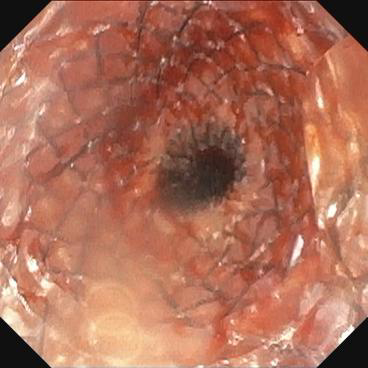

近日,pilipili 消化内科接诊了一位因胰胃间隙恶性肿瘤、食管狭窄,无法进食的91岁营养不良患者。患者入院后,在进行更换胃管时,发现普通胃管已无法通过,行胃镜检查中发现狭窄明显。经过院内专家团队的评估,决定采用超细胃镜尝试,并成功放置了空肠管。针对该患者高龄、身体虚弱、营养不良等实际情况,经与家属沟通,同意行内镜下放置食管支撑架。手术由陈东副主任医师和陈达主治医师完成,术后患者的食管狭窄得到缓解,可自主进食,生活质量得到了显著提升。

首选覆膜自膨式金属支架。ESGE 在食管支架置入术指南中,建议置入一个完全或部分覆膜的自膨式金属支架(fcSEMS/pcSEMS) 用于治疗恶性吞咽困难,有研究表明其移位率更低。在支架长度的选择上,根据食管肿瘤位置、长度和食管直径选择合适的食管支架,通常支架至少比病变长度长3-4 cm,使支架置入食管后支架远端超过狭窄段15-20 mm,近端高出病变20mm 左右,确保支架覆盖整个病变范围,但对于肿瘤邻近主动脉弓者,食管支架近端应超出主动脉弓上缘,以避免随着主动脉搏动,支架上极机械摩擦导致食管穿孔,甚至主动脉穿孔大出血。